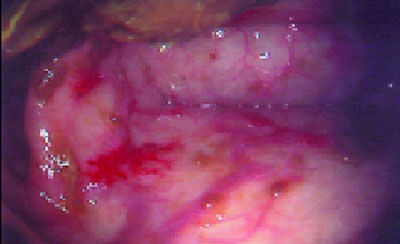

Εικ

όνα από θόλο στομάχου σε ασθενή με επιγαστρικό άλγος.

2. Πρόκειται για κυστικούς πολύποδες θόλου στομάχου. Στη σποραδική μορφή υπάρχει μικρός αριθμός πολυπόδων. Όταν υπάρχουν >10 πολύποδες, τότε χαρακτηρίζεται ως κυστική πολυποδίαση. Ενδοσκοπική αφαίρεση και follow up συστήνεται μόνο στην περίπτωση που συνυπάρχουν με σύνδρομο οικογενούς αδενωματώδους πολυποδίασης.